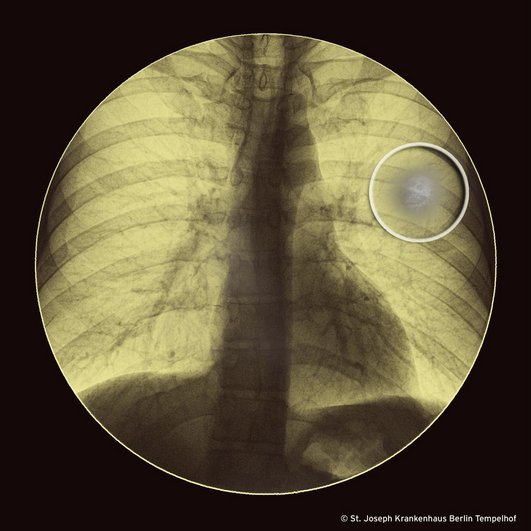

In der Thoraxübersichtsaufnahme sieht der Radiologe eine „rundlich flächige Verschattung im linken Oberfeld“ die unser Bild zeigt.

Die CT des Thorax bestätigt den Befund und präzisiert: Zentral im linken Oberlappen findet sich eine konsolidierende Infiltration mit einem Durchmesser von 20mm welche von einem schmalen Saum von Milchglasinfiltraten umgeben ist (Bild im nächsten Infektoskop).